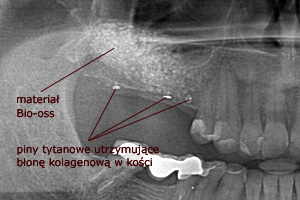

W każdej z metod, po odwarstwieniu błony Schneidera (błony śluzowej wyścielającej ściany zatoki), w wytworzoną przestrzeń wprowadzany jest materiał kościozastępczy będący zrębem dla powstawania nowej tkanki kostnej.